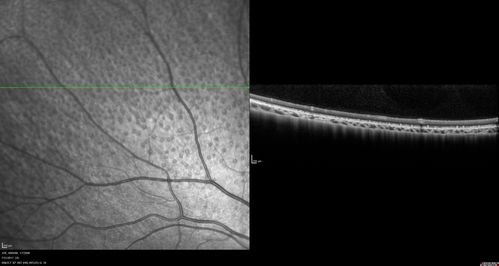

Fundus Albipunctatus

12 year old female with normal vision. She has 4 siblings all of whom have either white spots or spots on IR. Genetic testing by parents was deferred.